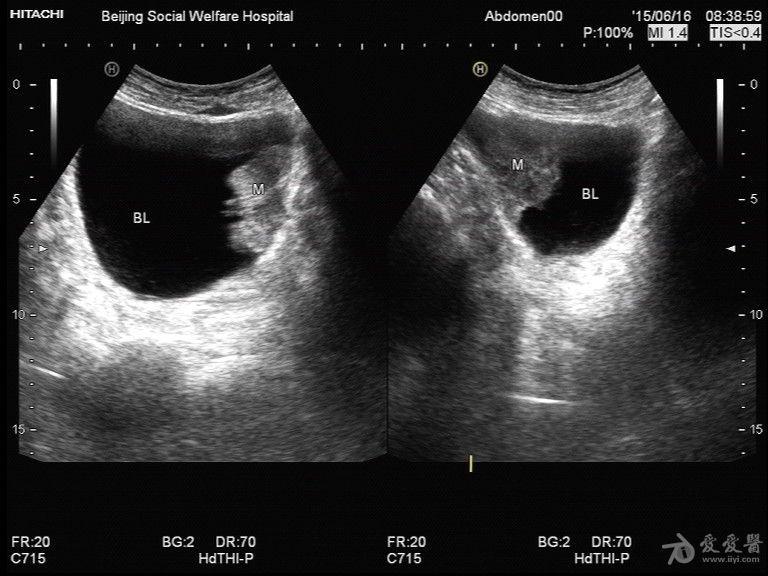

典型膀胱癌声像图一例

图片尺寸636x434